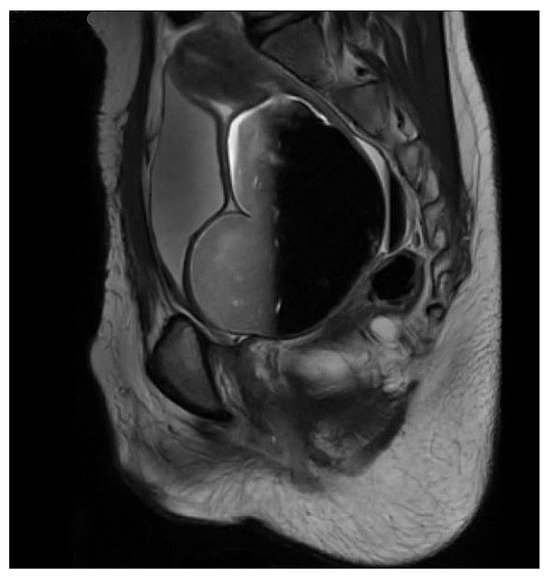

Figure 2.

MRI showing grossly dilated vagina and hematocolpos in a patient with prior repair of pelvic fracture urethral injury.

Occasionally, the vagina was also transected. Resultant scarring sometimes led to the formation of a vaginal septum. As a result, the proximal vagina and uterus could become compartmentalized and separated from the distal vagina. Affected patients presented with amenorrhea and hematocolpos. Diagnosis was made by demonstrating these findings on ultrasound. Intraoperative vaginoscopy was very important in such cases. Inability to visualize the cervix during intraoperative vaginoscopy confirmed the presence of a vaginal septum. These cases were treated with either laser incision of the septum or vaginal pull-through.